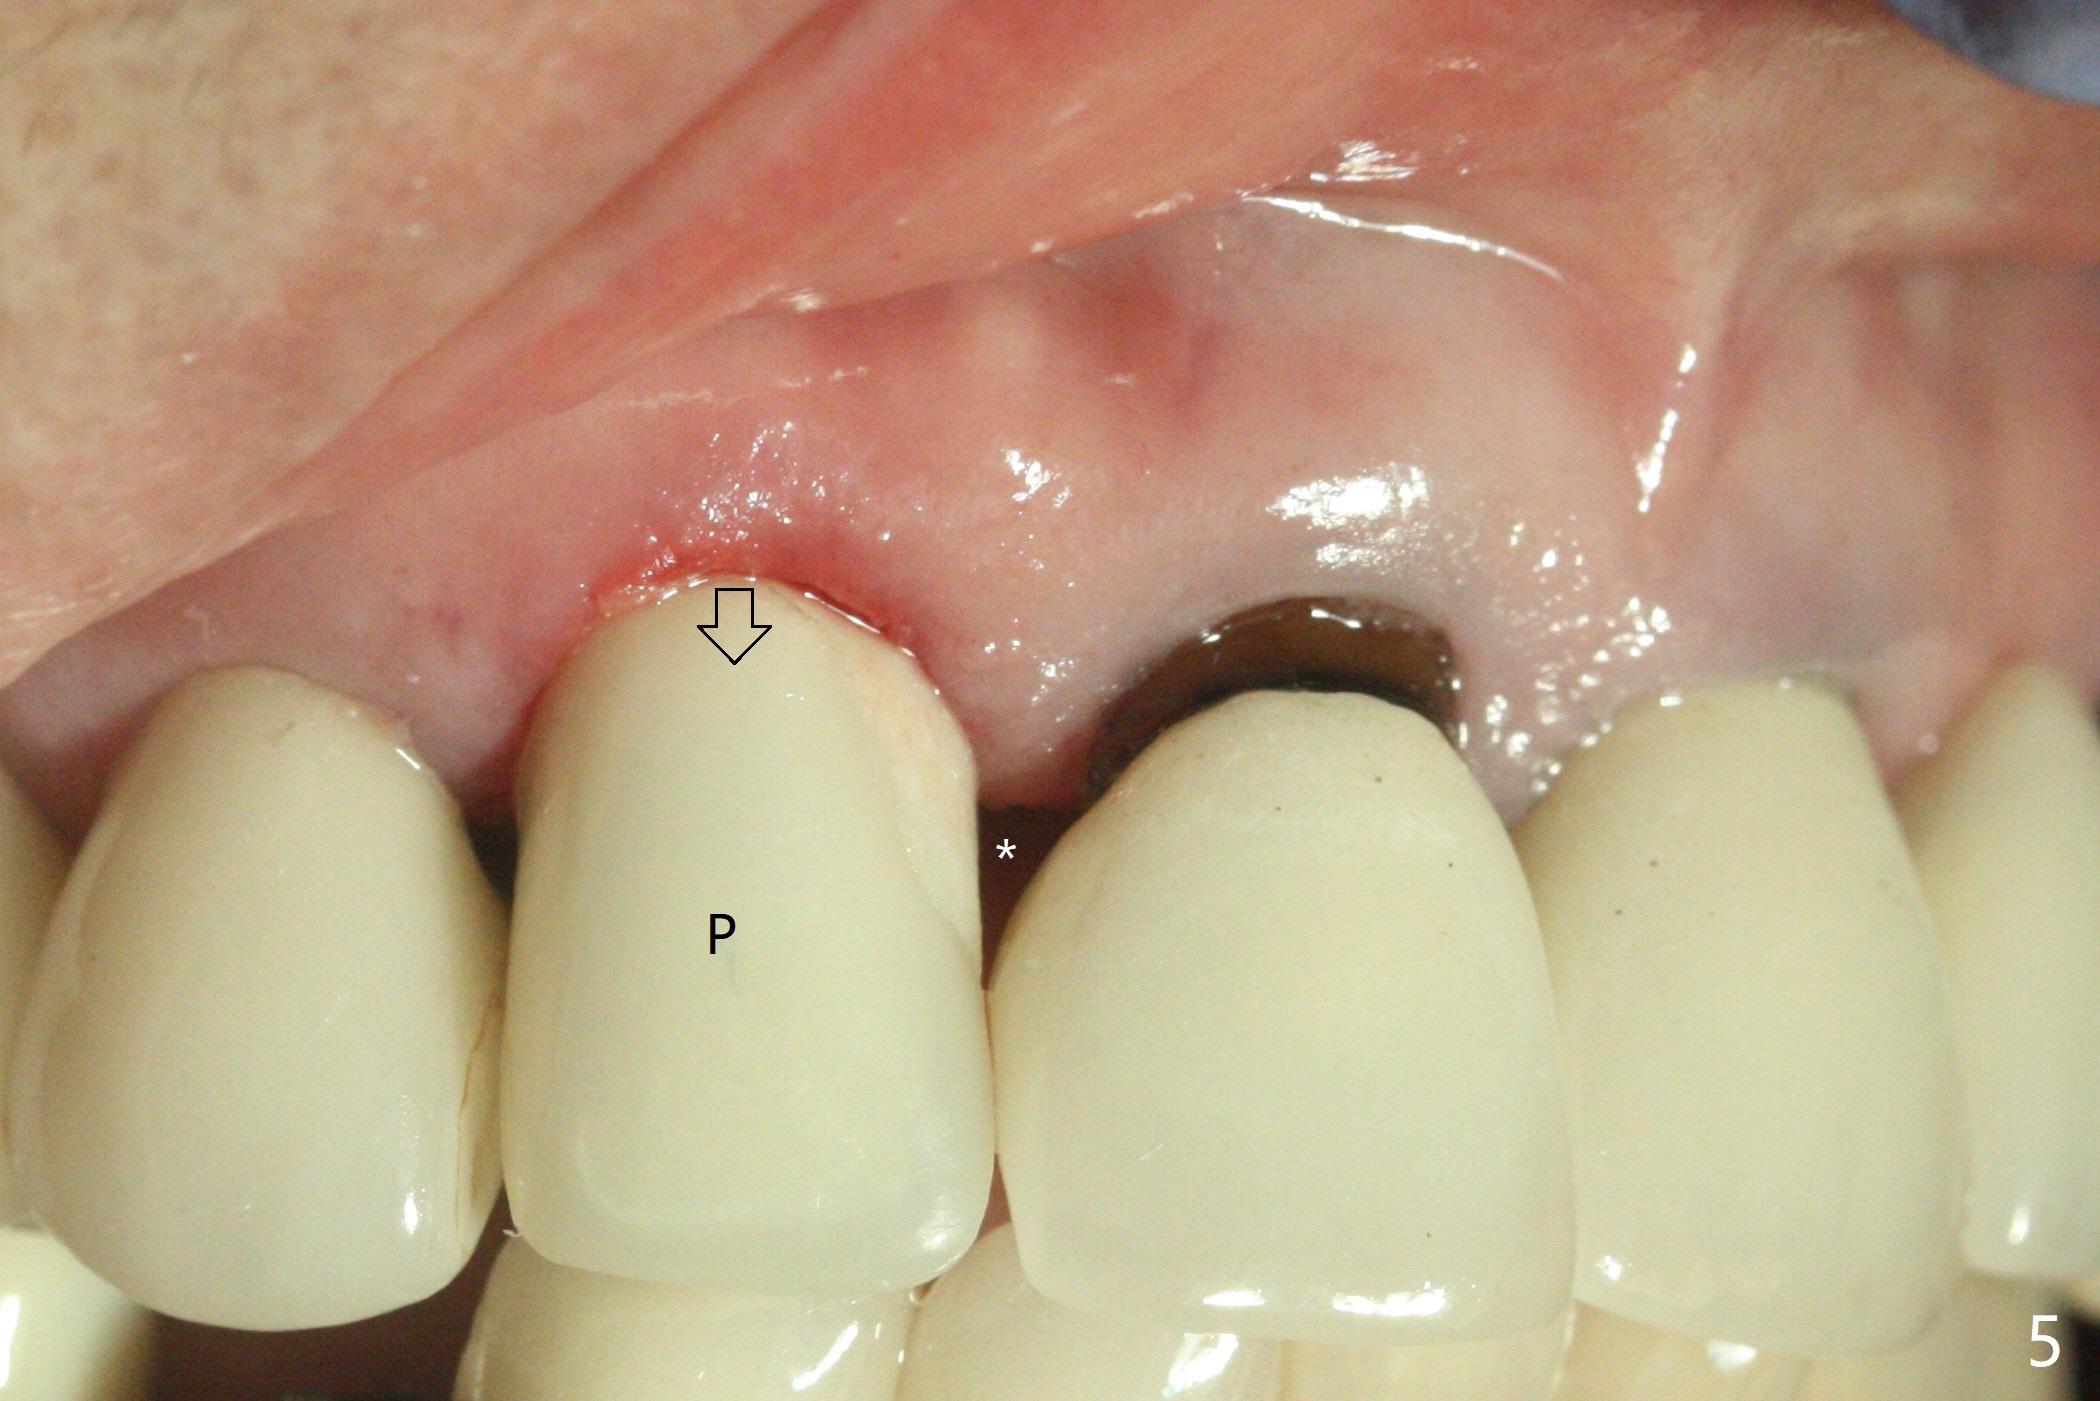

Immediate Embrasure Closure M